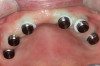

Fig 8. Conventional Locator attachments attached to the maxillary implants (top panel) and mandibular implants (bottom panel).

Figure 8

12-mm implants were placed; and at site No. 13, a 4.6-mm x 12-mm implant was placed. Conventional LOCATOR® abutments (Zest Dental Solutions; alternatively: ERA abutments, Sterngold; Ball abutments, Nobel Biocare) were attached to the implants (Figure 8). The existing maxillary prosthesis was relieved, adjusted, relined with a soft reline material (CHAIRSIDE® Soft Reline Material, Zest Dental Solutions; alternatively: Coe-Soft, GC America; Ufi Gel SC, VOCO), and placed in the oral cavity.